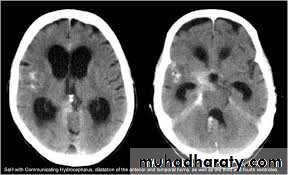

Non –obstructive ( communicating )

No obstruction of the ventricular pathway , but the absorption of the csf at the level of arachnoids' granulation is occluded secondary to lodge by blood clot or inflammatory cell or infection post meningitis most commonly to occur post SAH .

Hydrocephalous

2 typesObstructive ( non – communicating )